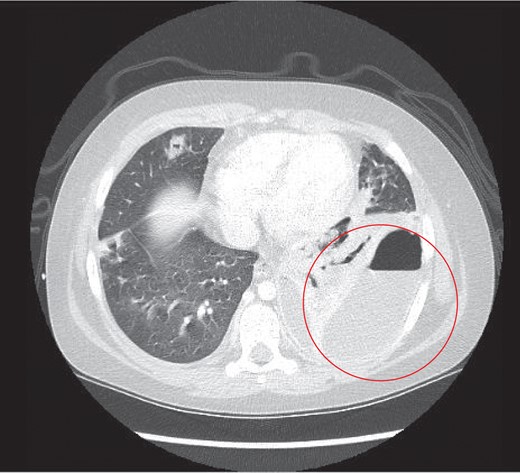

The child underwent a CT scan which demonstrated a large left sided empyema with an air fluid level (Fig. 2). The left lower lobe was collapsed with a multiloculated fluid collection. The appearances were suggestive of a necrotic lung abscess. The suggestion was that a Staphylococcus species was the most likely organism to account for the pattern of infection.

Thoracic CT study the next day, which revealed a large left sided lung empyema with an air fluid level. There was further consolidation and collapse within the left lower lobe and a multiloculated fluid collection.

A further finding on the CT was of a large thrombus within the left pulmonary vein extending into the left atrium and a segmental left lower lobar pulmonary embolus (Fig. 3). The left hemidiaphragm was intact. The abdomen and pelvis showed no further source or complication of sepsis.

Thrombus noted in the left pulmonary vein extending into the left atrium.